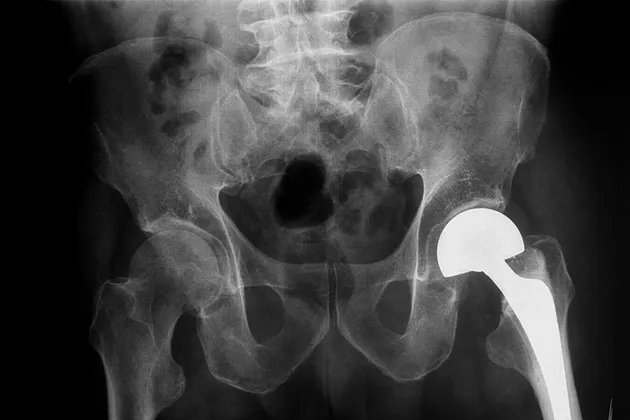

Imagine taking your car to a mechanic who has no clue how much a battery or muffler costs—and has no way of finding out. Substitute “artificial hip” for “battery” and “doctor” for “mechanic” and you get a pretty good picture of the convoluted market for medical implants. Asked to estimate the cost of common devices such as replacement knees or spinal screws, physicians at seven major academic hospitals in the U.S. were wrong 81 percent of the time, according to a January study published in the journal Health Affairs. The survey of 503 orthopedists at institutions including Harvard, Stanford, and the Mayo Clinic considered doctors’ answers correct if they came within 20 percent of what their hospital paid suppliers. The worst guesses ranged from a small fraction of the actual price to more than 50 times what the hospital paid.